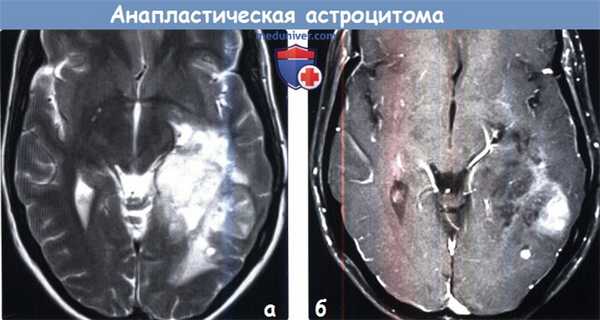

(а) МРТ, Т2-ВИ, аксиальный срез: у женщины 47 лет в лобной доле определяется гетерогенно гиперинтенсивное объемное образование, локализующееся преимущественно в белом веществе и распространяющееся на вышележащую кору. Хотя образование выглядит отграниченным от окружающих тканей, клетки опухоли часто обнаруживаются за пределами области изменений сигнальных характеристик.

(б) МРТ, постконтрастное Т1-ВИ, корональный срез: у этой же пациентки внутри объемного образования визуализируется участок контрастирования,. Характер контрастирования анапластической астроцитомы вариабелен: от отсутствия контрастирования до фрагментарного или узлового контрастирования. Большинство АА не накапливают контраст.3. МРТ при анапластической астроцитоме: